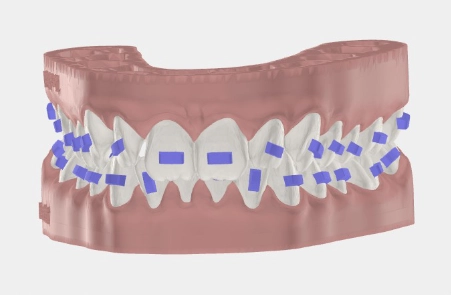

Hinter jeder erfolgreichen Aligner-Behandlung steht ein digitaler Plan. Mit modernster 3D-Technologie und gelenkzentrierter Diagnostik planen wir Ihre Zahnbewegungen präzise nach unserem Konzept KFO360° — noch bevor der erste Aligner gefertigt wird.

Wir kombinieren hochauflösende 3D-Scans mit Kiefergelenksdiagnostik, um eine Behandlung zu entwerfen, die zu Ihrem gesamten Kauapparat und Körper passt.

Expertengeführte Bewegungssimulation

Jede Zahnbewegung planen wir selbst — nicht die Aligner-Firma. Weil wir den Patienten kennen, passt jeder Schritt genau.

Individuelle Aligner-Herstellung

Ihre Aligner werden exakt nach dem Plan gefertigt — für optimalen Komfort und bestmögliche Ergebnisse.